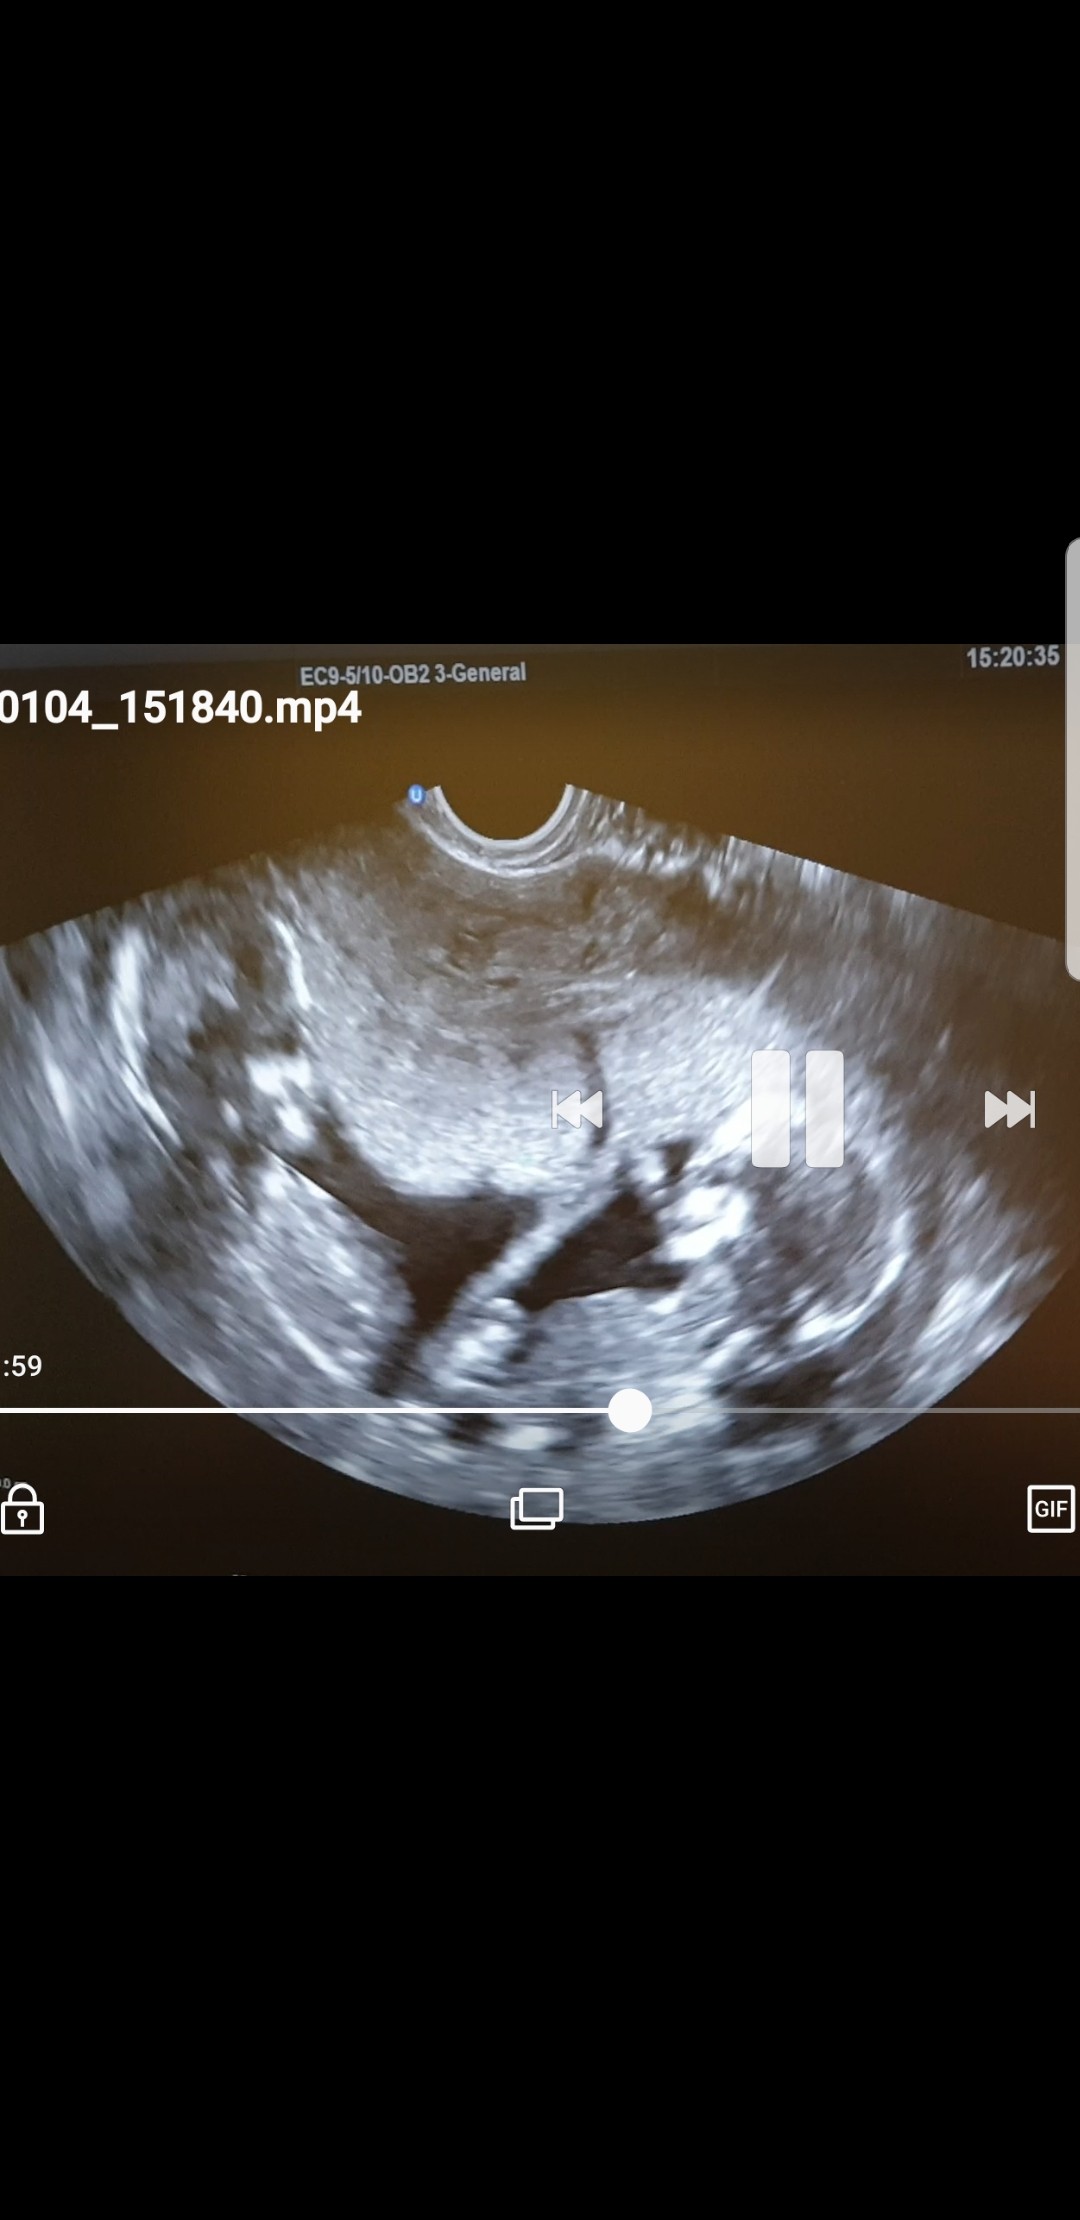

Witajcie Kochane ja po wizycie prenatalne badania w porządku dr.zbadał dzidzie rosną zdrowo na usg moje tulisie patrza na siebie [emoji173][emoji173]dziś 14t2dc kazał zrobić glukozę po obciążeniu bo na czczo 95 :( muszę wrócić do diety dla insulionopornych bo w święta pofolgowalam i tak do tej pory nie mogę się pozbierać pozdrawiam Was kochane sorki za zdjęcie ale robione na szybko z filmu Zobacz załącznik 930403

Witajcie Kochane ja po wizycie prenatalne badania w porządku dr.zbadał dzidzie rosną zdrowo na usg moje tulisie patrza na siebie ❤❤dziś 14t2dc kazał zrobić glukozę po obciążeniu bo na czczo 95 :( muszę wrócić do diety dla insulionopornych bo w święta pofolgowalam i tak do tej pory nie mogę się pozbierać pozdrawiam Was kochane sorki za zdjęcie ale robione na szybko z filmu Zobacz załącznik 930403